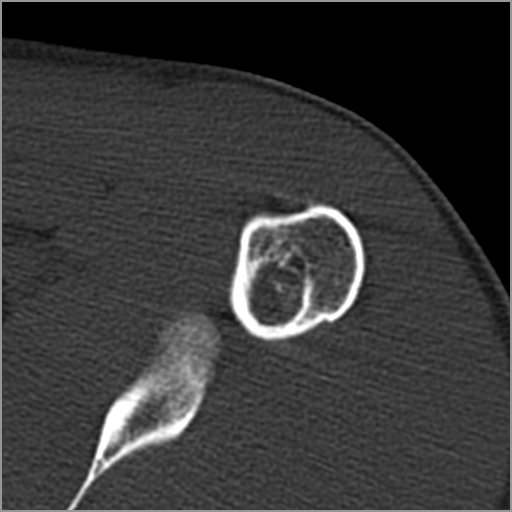

以下是引用zxd95在2008-7-19 18:45:00的发言:[br]囊性病灶边缘硬化、皮质变薄但连续——提示生长时间长、良性病变——考虑左肱骨头骨囊肿。[br]

以下是引用杀毒软件在2008-7-19 18:55:00的发言:[br]考虑:骨巨细胞瘤可能性大